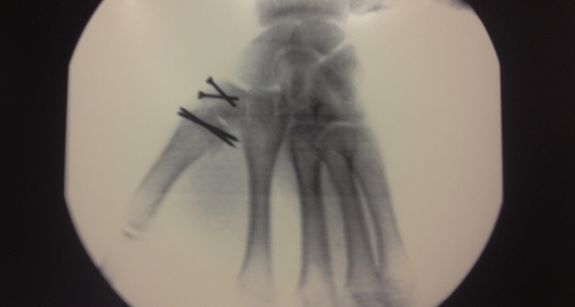

A helyszínen megröntgenezték, begipszelték kézfejét, és hétfői kontrollra ítélve engedték el a pályaorvosok. A későbbi kórházi vizsgálatok két eltört és elmozdult kézcsontot állapítottak meg. Este a kézfej felnyitása nélkül drótokkal rögzítették a problémás első kézközépcsontot és trapézcsontot. A szerdai röntgen ismét elmozdulást mutatott így csütörtök reggel újabb műtét következett. Ekkor ismét altatásban, de már vágással és csavarral is rögzítve oldották meg a problémát, majd szombaton a késői órákban engedték haza Viktort a kórházból. Most több kontroll és egy újabb műtét vár rá, amikor a csavarok és a drótok eltávolítására kerül sor. Ezt követően kezdődhet meg a rehabilitáció.